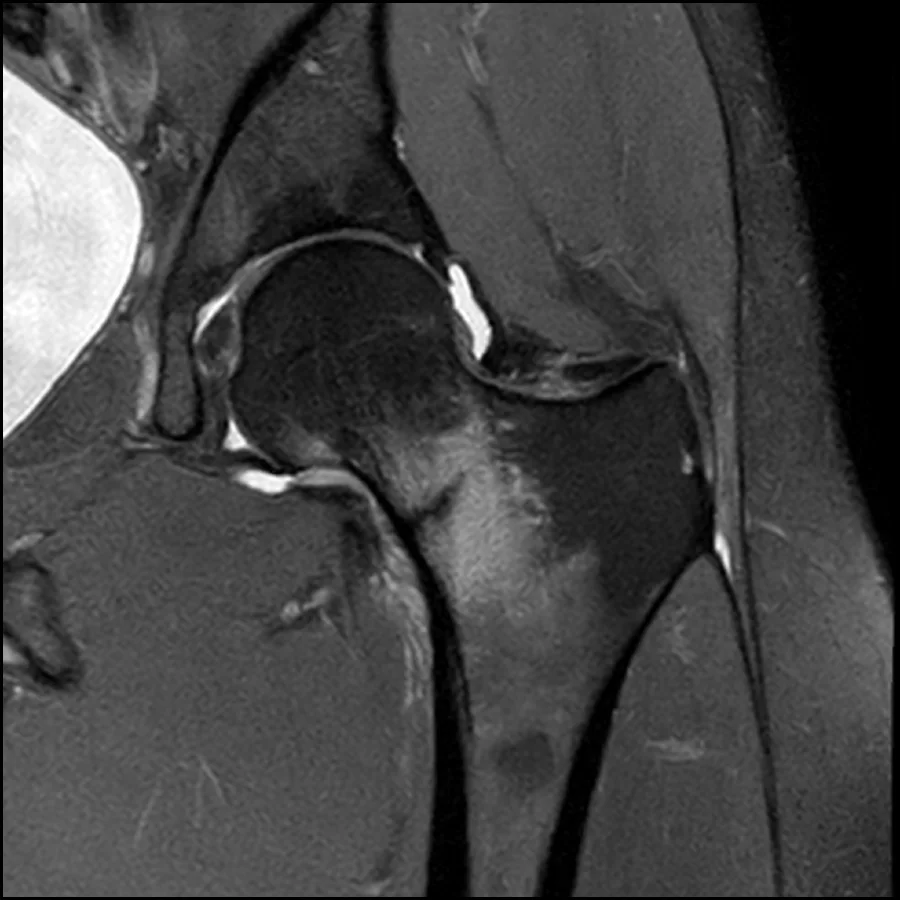

- Early diagnosis can be challenging, as initial X-rays may appear normal; MRI is the most sensitive imaging method for detection.

One of the main challenges is that X-rays may not show early hairline fractures. In the initial stages, the crack in the bone is often too small to be visible on standard radiographs. This is why patients may initially receive a normal X-ray result despite ongoing symptoms.

For more accurate detection, advanced imaging is often required. MRI scans are considered the most sensitive method because they can detect early bone stress reactions before a visible fracture develops. Bone scans can also be useful, as they highlight areas of increased bone activity associated with stress injury.